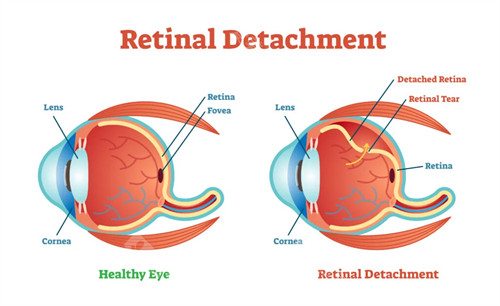

作为首都医学大学附属北京同仁医院眼底病科的“定海神针”,他擅长复杂眼底病诊疗,尤其对视网膜脱离、糖尿病视网膜病变等疾病的手术处理堪称业内标杆。